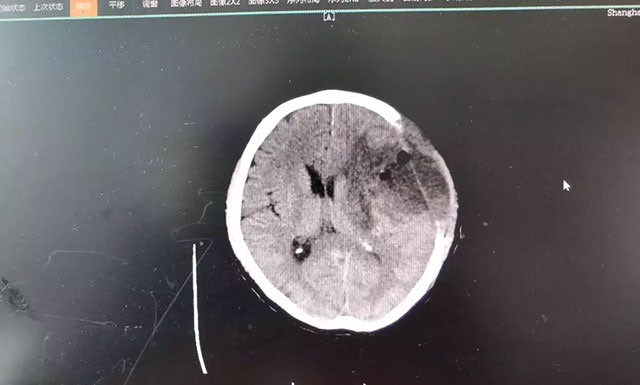

“是不是中风了?”家人看情况不妙,赶紧将钱先生送到当地医院检查。CT影像报告显示,患者大脑左颞叶占位。随后几天,钱先生的症状出现反复和恶化,考虑到当地医疗资源条件较为有限,家人将其转至上海蓝十字脑科医院,作进一步诊断治疗。

在蓝十字脑科医院,头颅磁共振增强扫描影像进一步明确:钱先生左额颞叶占位性病变,类椭圆形团块状异常信号大小约4.3*3.2cm,边界不清,病灶周围有明显水肿。从症状体征和影像学资料判断,钱先生患上脑胶质瘤的可能性很大,通过对患者术后病理标本检验,也印证了该结论。